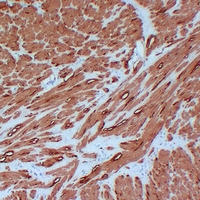

Immunohistochemical analysis of Actin pan staining in human cardiac muscle formalin fixed paraffin embedded tissue section. The section was pre-treated using heat mediated antigen retrieval with sodium citrate buffer (pH 6.0). The section was then incubated with the antibody at room temperature and detected using an HRP conjugated compact polymer system. DAB was used as the chromogen. The section was then counterstained with haematoxylin and mounted with DPX. -